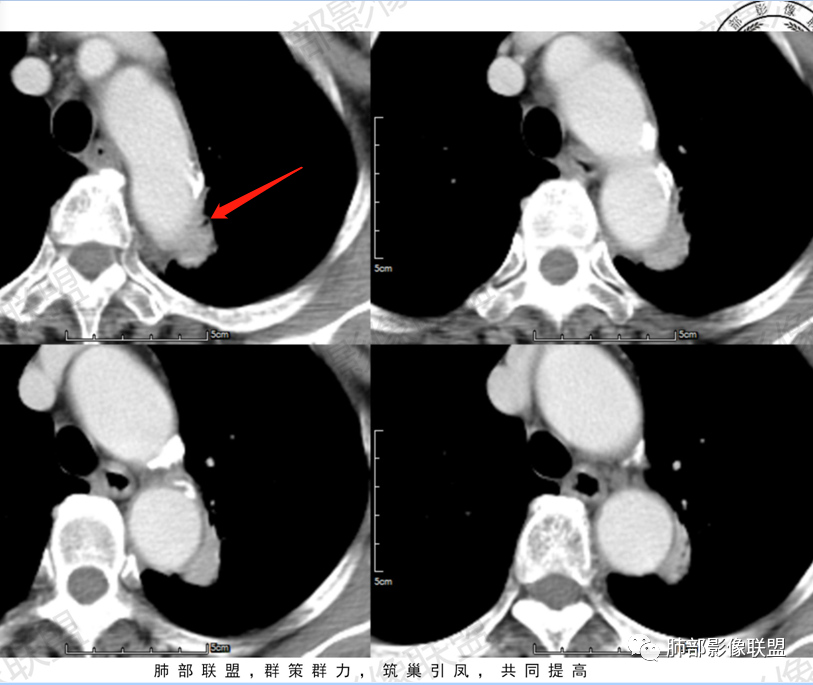

尘缘:支气管进入并堵塞

尘缘:病灶沿主动脉匍匐样生长,但整体明显膨隆,胸膜牵拉凹陷,局部有小喇叭口样改变。

尘缘:边界清楚的GGO。

尘缘:局部血管增粗,扭曲

尘缘:局部有淋巴管增粗,小叶间隔增厚,提示癌淋可能。

尘缘:最后就是强化,虽然是明显渐进性强化,要考虑炎性可能,但腺癌明显渐进性强化的并不少见。

所以,很明确的支持腺癌。

2.轴位显示主动脉弓旁依势傍行弧形高密度影,隐约见尖后段支气管进入并截止。病灶边界较清楚,见血管结构及线性影与邻近肺组织相延伸。

3.病灶渐进性显著均匀强化!动脉期未见主动脉腔异常通道。

4.冠矢状位病灶于弓上部偏后局限性“贝雷帽”状突起,提示病灶有局部膨隆特点,且病灶上份及后份饰以边缘较清楚磨玻璃影。